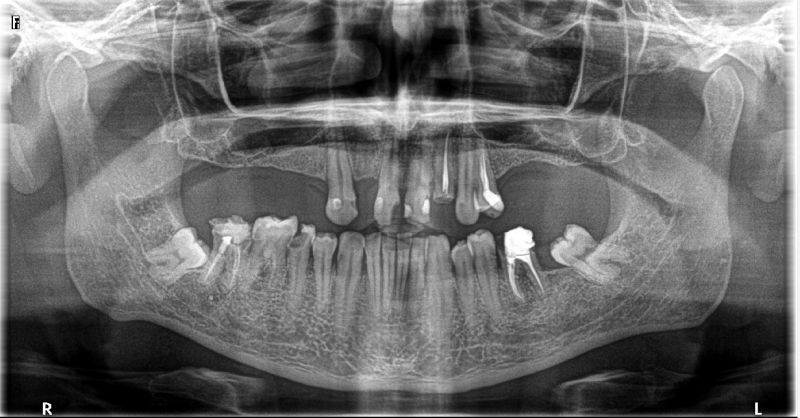

Wykonana praca protetyczna:

- most pełnołukowy na sześciu implantach

- korony na zęby własne w łuku dolnym

- korony na implantach w miejscach braków zębów

- odbudowa flow-injection zębów dolnych przednich